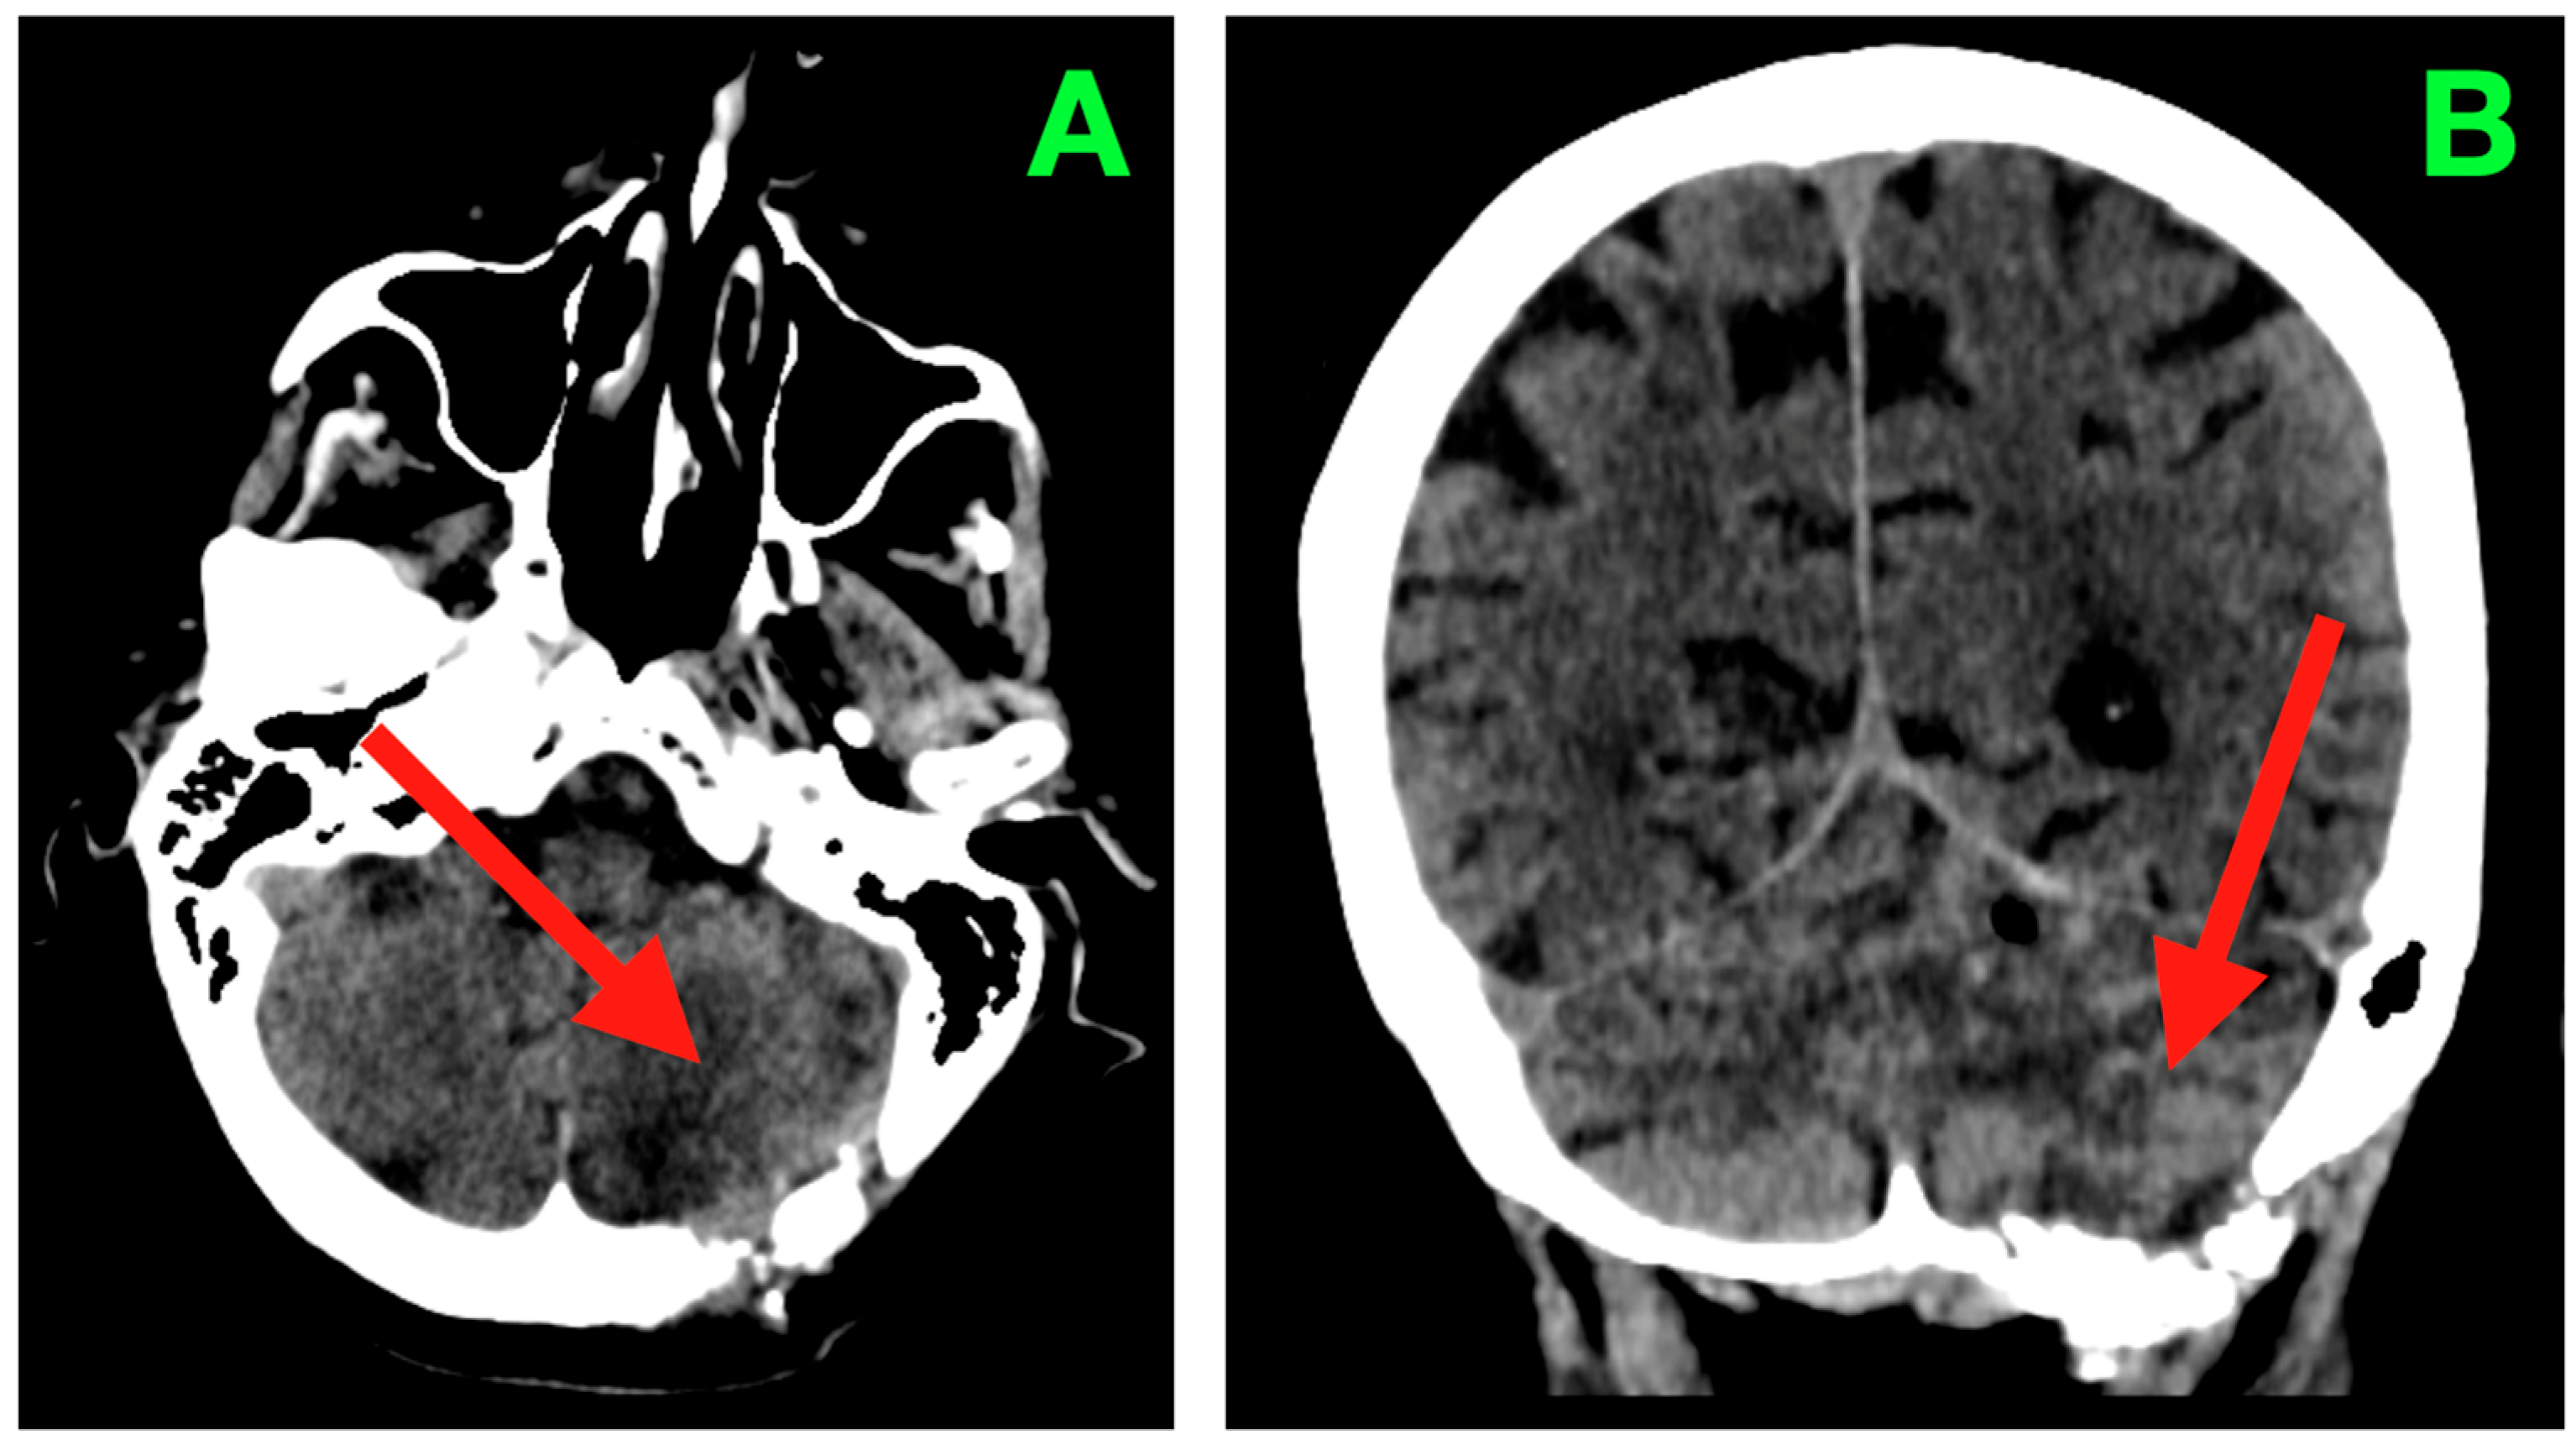

2. Case Presentation